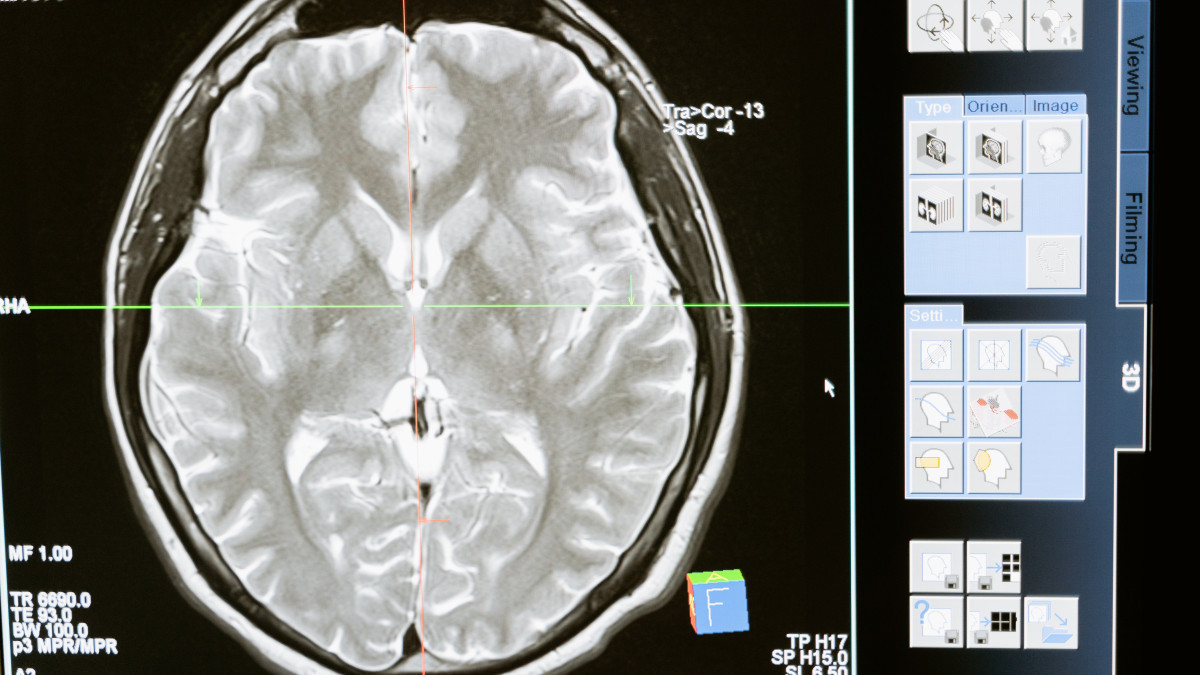

After a massive five-year effort, researchers have unveiled an "atlas" that gives an unprecedented look at the intricacies of the human brain, El.kz cites upi.com.

The atlas, which will be available to researchers everywhere, can be seen as similar to the atlases we all know: a book of maps.

But this one catalogues human brain cells and their striking diversity and complexity. Going forward, the atlas will help other researchers "navigate" the brain, said Bing Ren, a professor at the University of California, San Diego, who was part of the research effort.

The atlas encompasses more than 3,000 types of brain cells, and gives insight into how they vary from one person to another, how they differ from non-human primates' brain cells, how particular brain cell types are related to specific diseases, and more.

The ultimate goal, Ren and other experts said, is to better understand the workings of the human brain -- and what goes wrong in the range of neurological and psychiatric conditions that plague humans, from Alzheimer's to depression to schizophrenia.